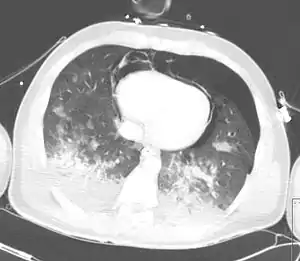

A chest CT scan revealing pulmonary contusions, pneumothorax, and pseudocysts

Computed tomography (CT scanning) is a more sensitive test for pulmonary contusion,[6][33] and it can identify abdominal, chest, or other injuries that accompany the contusion.[38] In one study, chest X-ray detected pulmonary contusions in 16.3% of people with serious blunt trauma, while CT detected them in 31.2% of the same people.[45] Unlike X-ray, CT scanning can detect the contusion almost immediately after the injury.[43] However, in both X-ray and CT a contusion may become more visible over the first 24–48 hours after trauma as bleeding and edema into lung tissues progress.[46] CT scanning also helps determine the size of a contusion, which is useful in determining whether a patient needs mechanical ventilation; a larger volume of contused lung on CT scan is associated with an increased likelihood that ventilation will be needed.[43] CT scans also help differentiate between contusion and pulmonary hematoma, which may be difficult to tell apart otherwise.[47] However, pulmonary contusions that are visible on CT but not chest X-ray are usually not severe enough to affect outcome or treatment.[37]